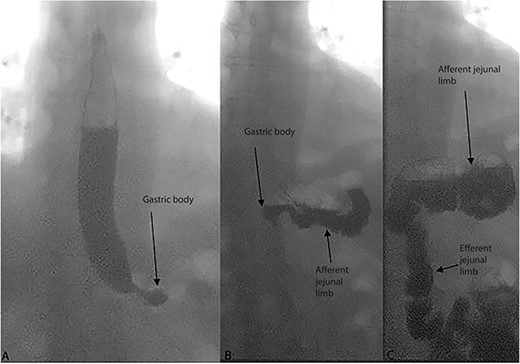

The patient was subsequently referred to gastroenterology clinic for further evaluation. An upper endoscopy was performed, which showed normal gastric bypass anatomy, aside from a blind, afferent jejunal limb measuring 9 cm, raising suspicion for CCS (Fig. 2). The rest of the endoscopic exam was unremarkable. The patient also underwent an upper gastrointestinal fluoroscopy series using barium, which confirmed filling of the long afferent limb first before entering the alimentary or Roux limb (Fig. 3). The patient reported replication of her symptoms with contrast bolus passage during the fluoroscopic exam.

Sequential images of dynamic upper gastrointestinal tract fluoroscopy examination with barium meal in the patient. Opacification is first seen in the esophagus and gastric body (A), followed by the afferent jejunal (blind) limb (B) and last the efferent jejunal (alimentary/Roux) limb (C).